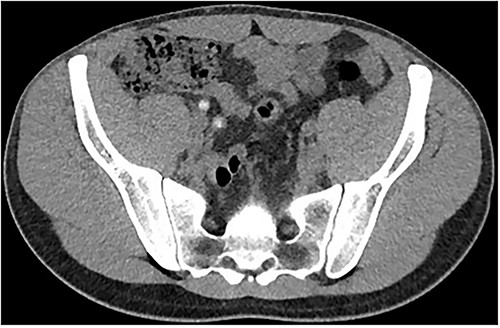

Two days following stent removal, the patient developed acute onset right lower quadrant and flank pain. A non-contrast CT of the renal tract was obtained to assess for procedure or stone-related complications. The scan demonstrated two distinct retained stones within the proximal right ureter, with associated moderate ureteronephrosis. Additionally, within the right lower quadrant of the abdomen, a radiopaque vermiform entity was demonstrated (Figs 1–3). This entity was not pathological, however, represented a normal appendix that had, consequent to contrast administration during a urological procedure, become filled with contrast secondary to vicarious contrast excretion.

Sagittal imaging, depicting the base of structure arising from the caecum.